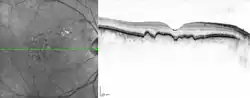

Drusen associated with aging and macular degeneration are distinct from another clinical entity, optic disc drusen, which is present on the optic nerve head.[2] Both age-related drusen and optic disc drusen can be observed by ophthalmoscopy. Optical coherence tomography scans of the orbits or head, calcification at the head of the optic nerve without change in size of globe strongly suggests drusen in a middle-age or elderly patient.

Mishra, S; Goel, S; Roy, SS; Garg, B; Parvin, M; Saurabh, K; Roy, R (January 2019). "Multimodal imaging characteristics of refractile drusen". Indian Journal of Ophthalmology. 67 (1): 128–129. doi:10.4103/ijo.IJO_867_18. PMC 6324114. PMID 30574912.